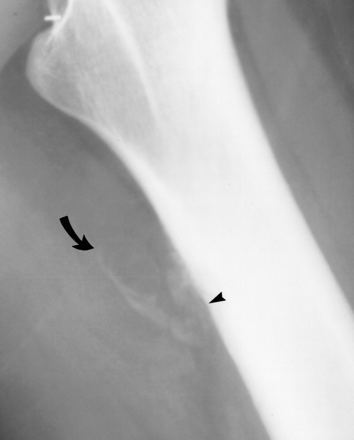

The cause of calcium hydroxyapatite crystal deposition in or near a tendon is unclear. It may be related to degeneration of a tendon with age, as a result of recurrent trauma, local hypoxia or metabolic factors. The leading theory at present is that calcific tendinitis is a primary disorder in susceptible tendons. The final pathway is likely to be local hypoxia leading to fibrocartilaginous metaplasia and subsequent calcification. Cortical reaction is caused by the local inflammatory response incited by the deposition of calcium in the affected tendon insertions. The periosteal reaction may have an aggressive appearance that can be confused with malignancy, particularly juxtacortical lesions.

Plain x-rays can be difficult to interpret as the calcified area overlies the bone on standard projections. Additionally there may be cortical reaction to the tendonitis mimicking other pathology. Therefore it is not unusual for a bone scan to show increased uptake.